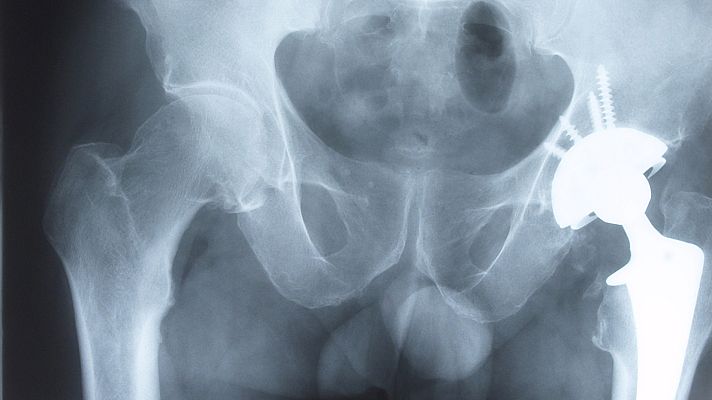

Sanidad asegura que las incidencias con las prótesis son "puntuales" y que se mejorarán los controles

El Ministerio de Sanidad se ha reunido con las asociaciones científicas y organismos profesionales médicos y farmacéuticos para tratar la seguridad de los dispositivos médicos y productos sanitarios, cuestionada por una investigación periodística a nivel internacional coordinada por el Consorcio Internacional de Periodistas de Investigación (ICIJ). Los representantes de el Consejo General de Colegios Oficiales de Médicos de España (CGCOM) comparten el mensaje de tranquilidad que ha lanzado la ministra, pero también han pedido que ese refuerzo de controles.